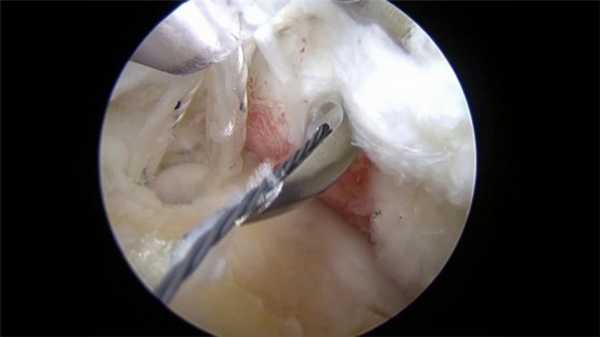

Обычно используется два/три прокола. В один вводится артроскоп, оснащенный источников света и микроскопической видеокамерой, которая передает изображение на монитор. Это позволяет подробно разглядеть все структуры. Одна или два других пункции используются для введения микрохирургических инструментов, необходимых для проведения операции.

Вид изнутри на сустав.

Такая методика обеспечивает высокую точность оперирования, минимальность вмешательства, отсутствия послеоперационных осложнений и быстрый период реабилитации. Особой актуальностью процедура пользуется среди спортсменов, которым необходимо быстро восстановиться и продолжить тренировки.